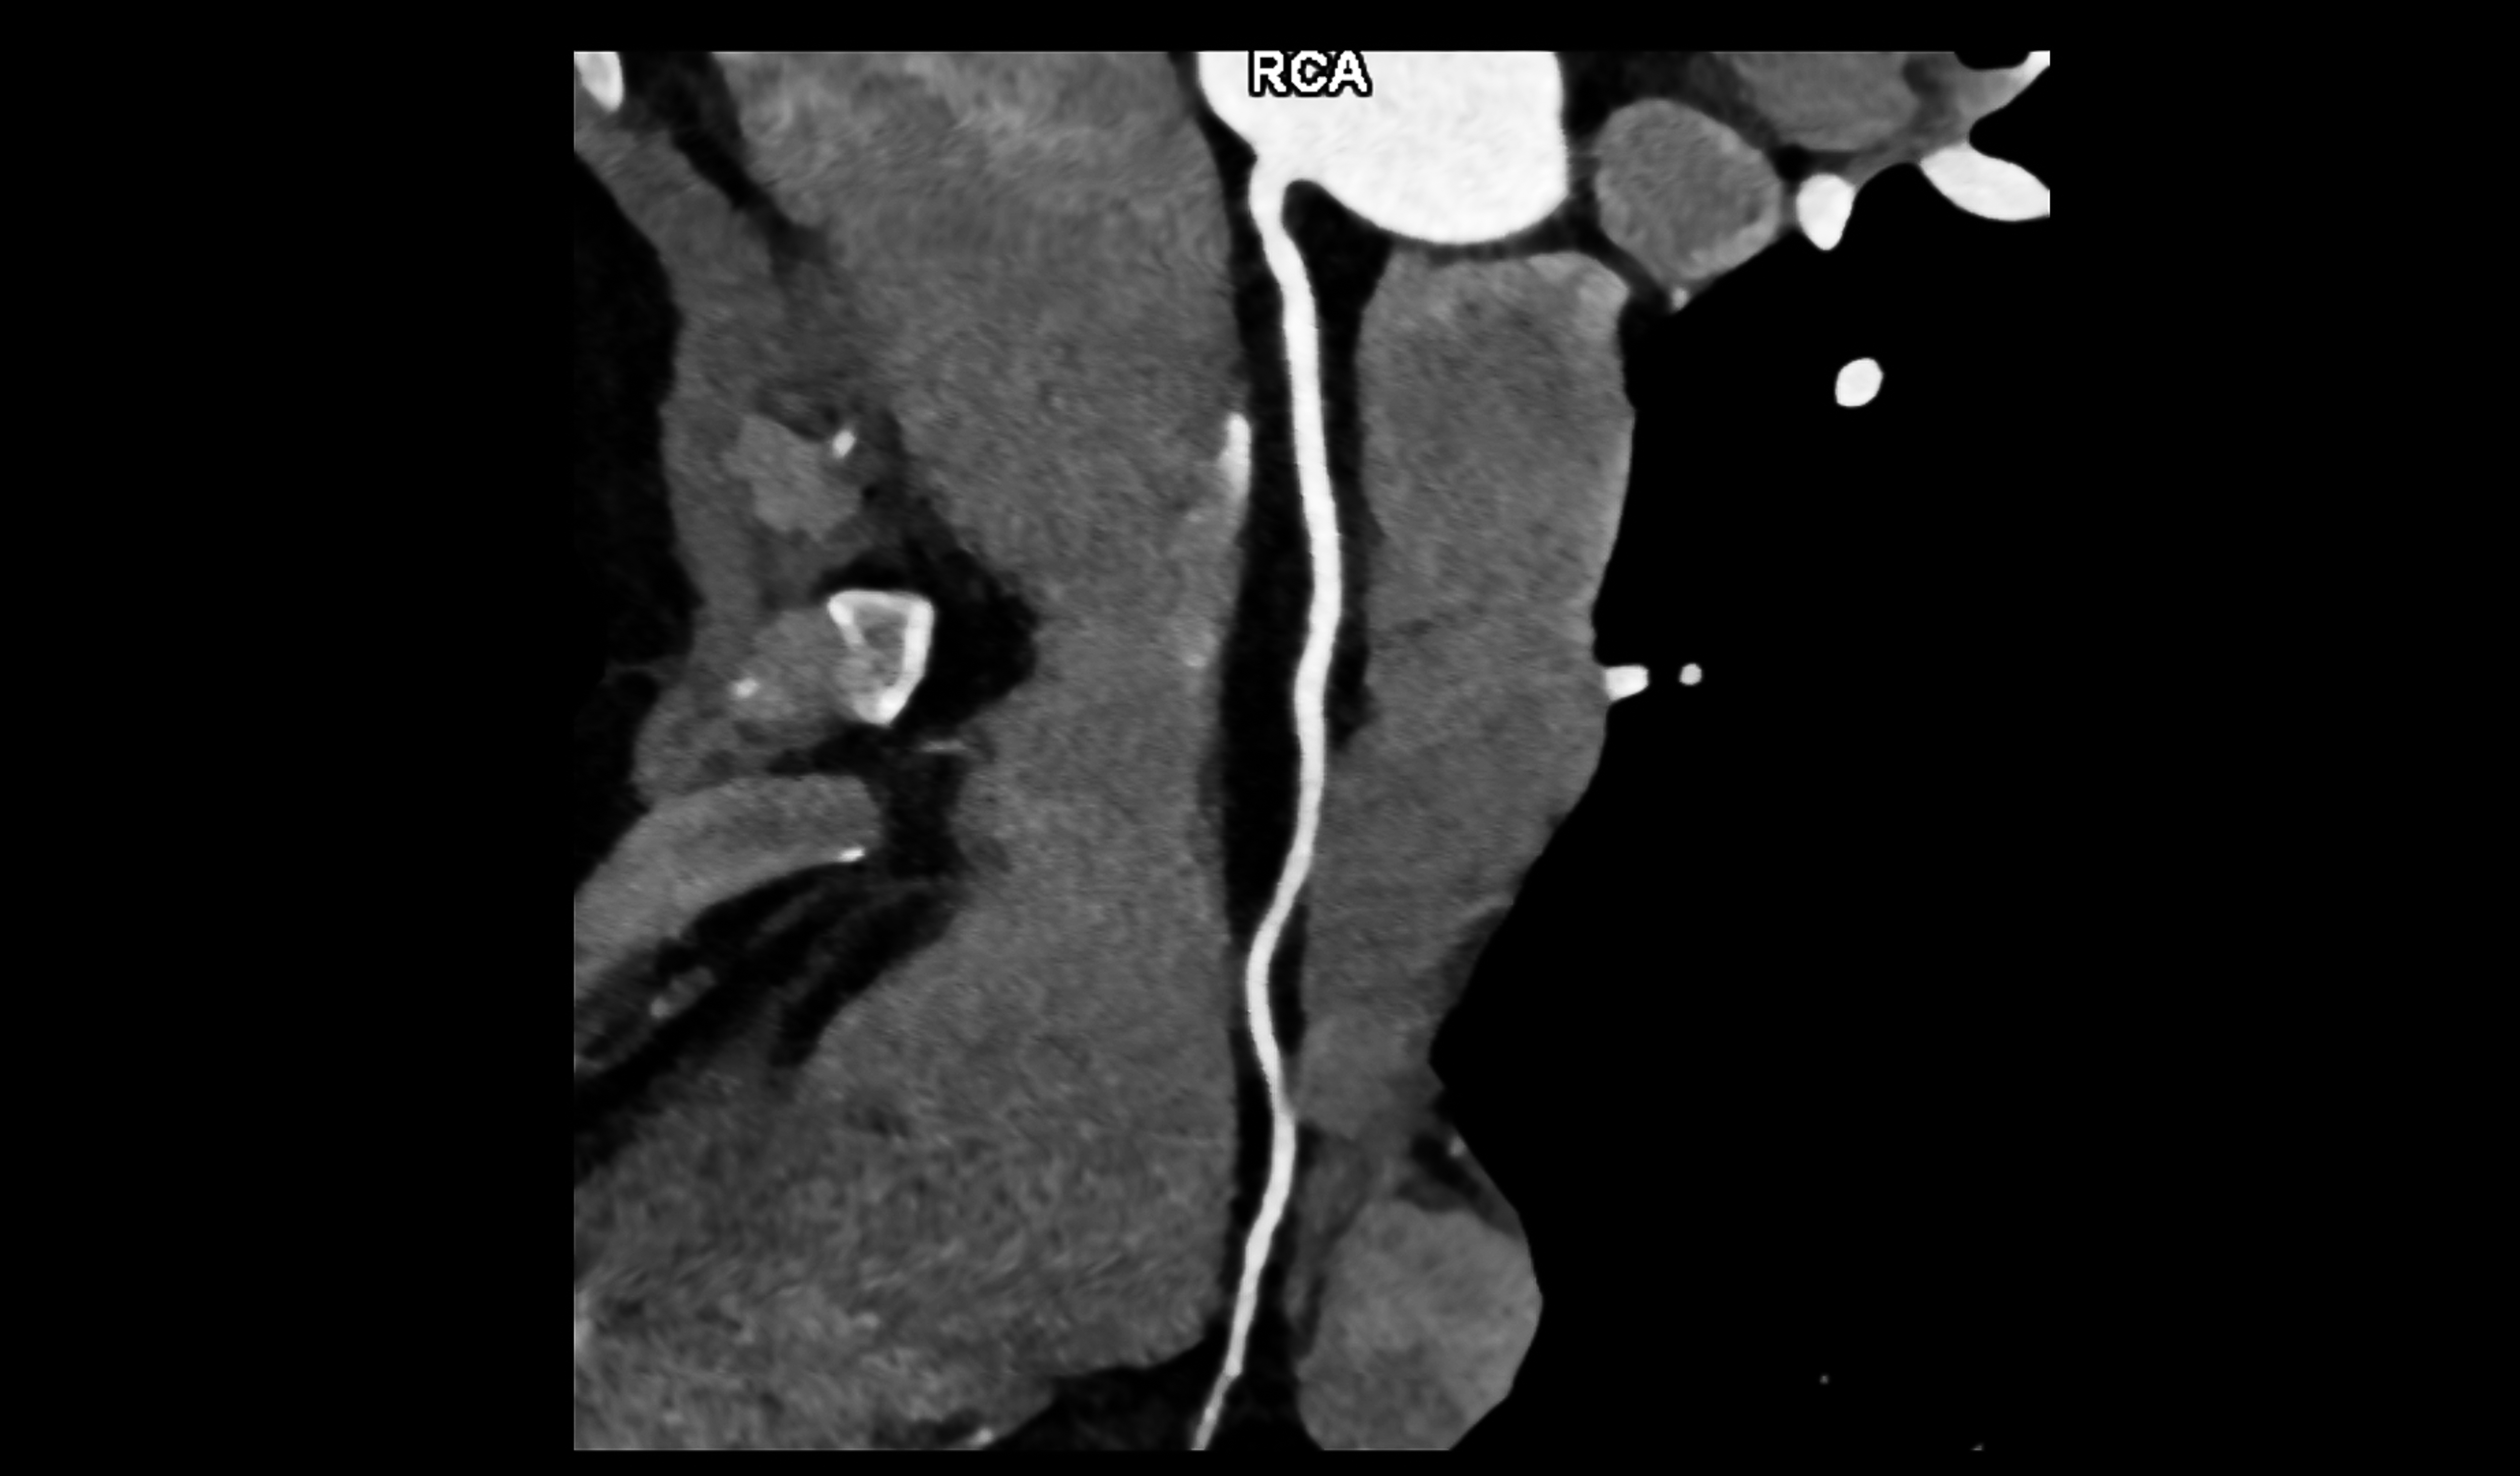

A Heart CT Scan - Multi-planar reconstruction of the right coronary artery (Multiplanar reconstruction, MPR : You can understand that you look at the blood vessels in a straight line though reconstruction program.